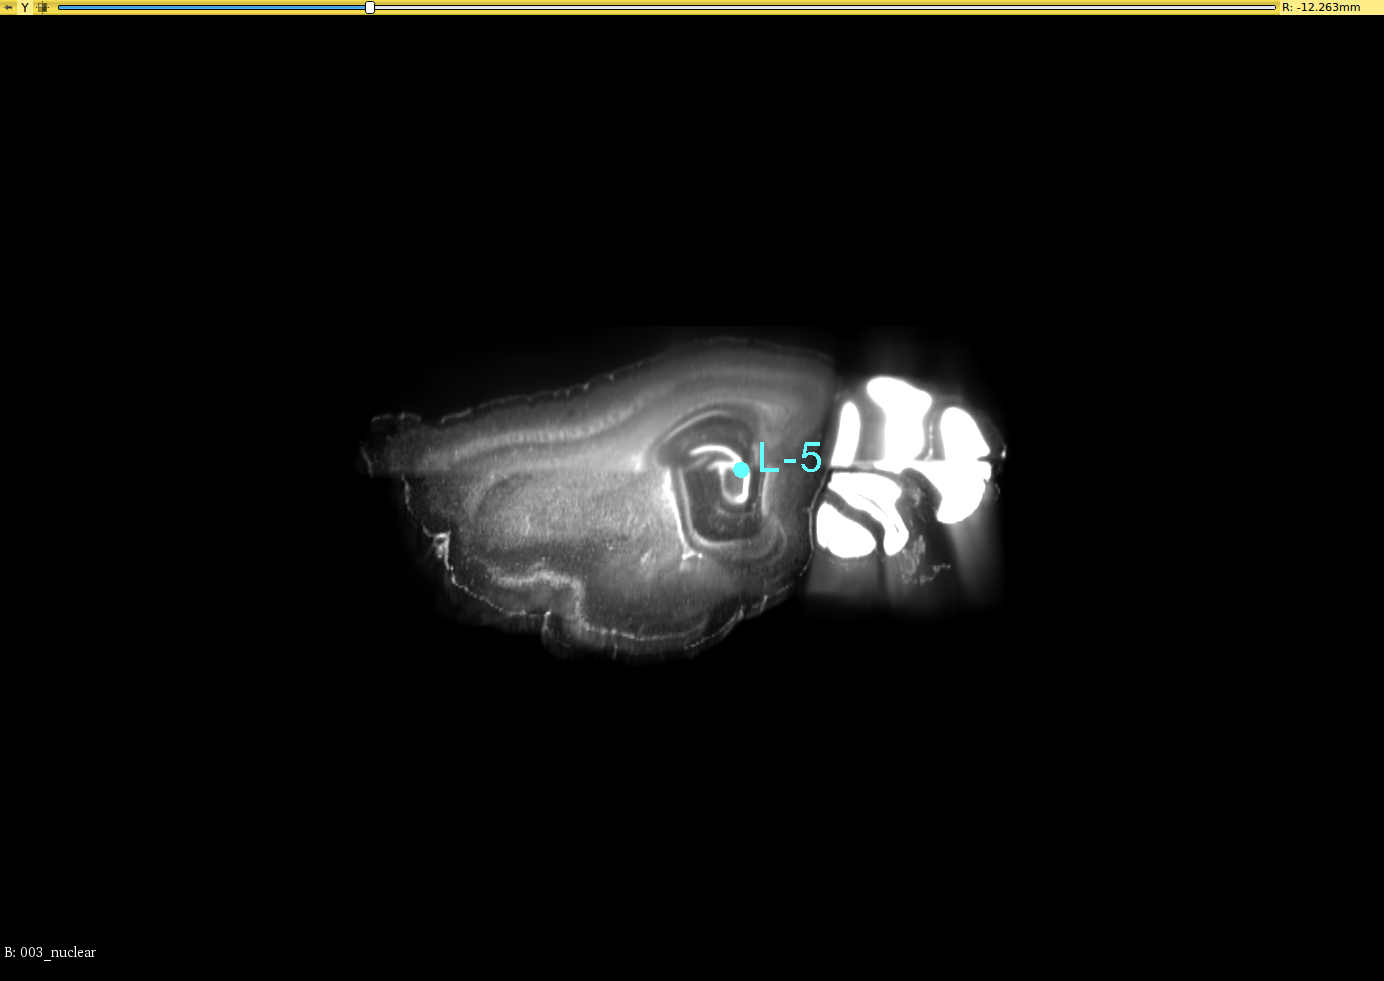

To validate the registration performance of the proposed methods and comparing the baseline methods in a more objective manner, a landmark registration test is conducted. In the CUBIC dataset, three brains are used to test the registration performance. In the landmark test, the same dataset is used for the performance validation. 12 landmarks are selected and all of these landmarks are selected where their positions vary in all three axis. 3D slicer tool is used to select the landmarks for this experiment from the CUBIC brains. A set of selected landmarks are shown in Figure 7. Table 3 shows the results of the 3D landmark registration by proposed InvGAN method and other baseline methods. The Euclidean distance between the registered landmarks and reference landmarks are presented in mm. For optimisation-based ANTS and Elastix tools, the same parameter sets are used to register landmarks selected from moving image and fixed image. After the registration, the output point locations are compared with reference point locations in the fixed image. For the deep-learning-based VoxelMorph and InvGAN, the deformation values in X,Y and Z are extracted from the same voxel location of the selected landmark’s voxel location. After applying deformation to the landmarks, the new position is compared with that of corresponding reference points in the fixed image.

Refer to caption

(a) Brain-1

(b) Segittal View

(c) Coronal View

(d) Corresponding Points in Brain003

(e) Segittal View

(f) Coronal View

(g) Brain-2

(h) Segittal View

(i) Coronal View

(j) Corresponding Points in Brain-3

(k) Segittal View

(l) Coronal View

Figure 7: 3D Landmarks